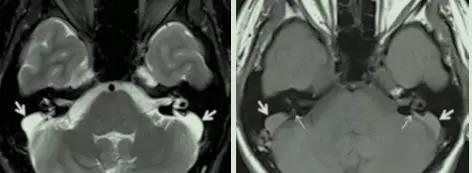

而目前高分辨率颞骨CT与内耳核磁是诊断本病的金标准。在CT上可以发现前庭导水管骨性结构的扩大(半规管总脚到前庭水管外口1/2直径大于1.5mm)。在核磁上可以看到内淋巴管和囊的扩大。